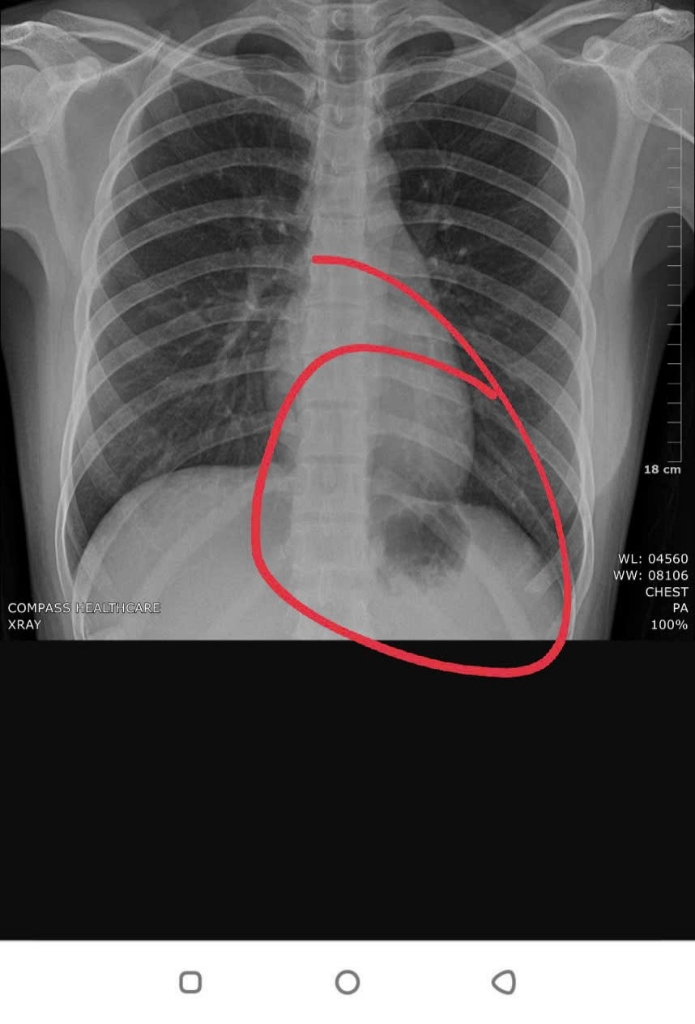

Em đánh dấu vị trí em nghi ngờ

Dạ bác cho em hỏi cục này là gì vậy ạ , em cảm ơn bác rất nhiều ạ

Bình thường có gì đâu em

Không bất thường nhé